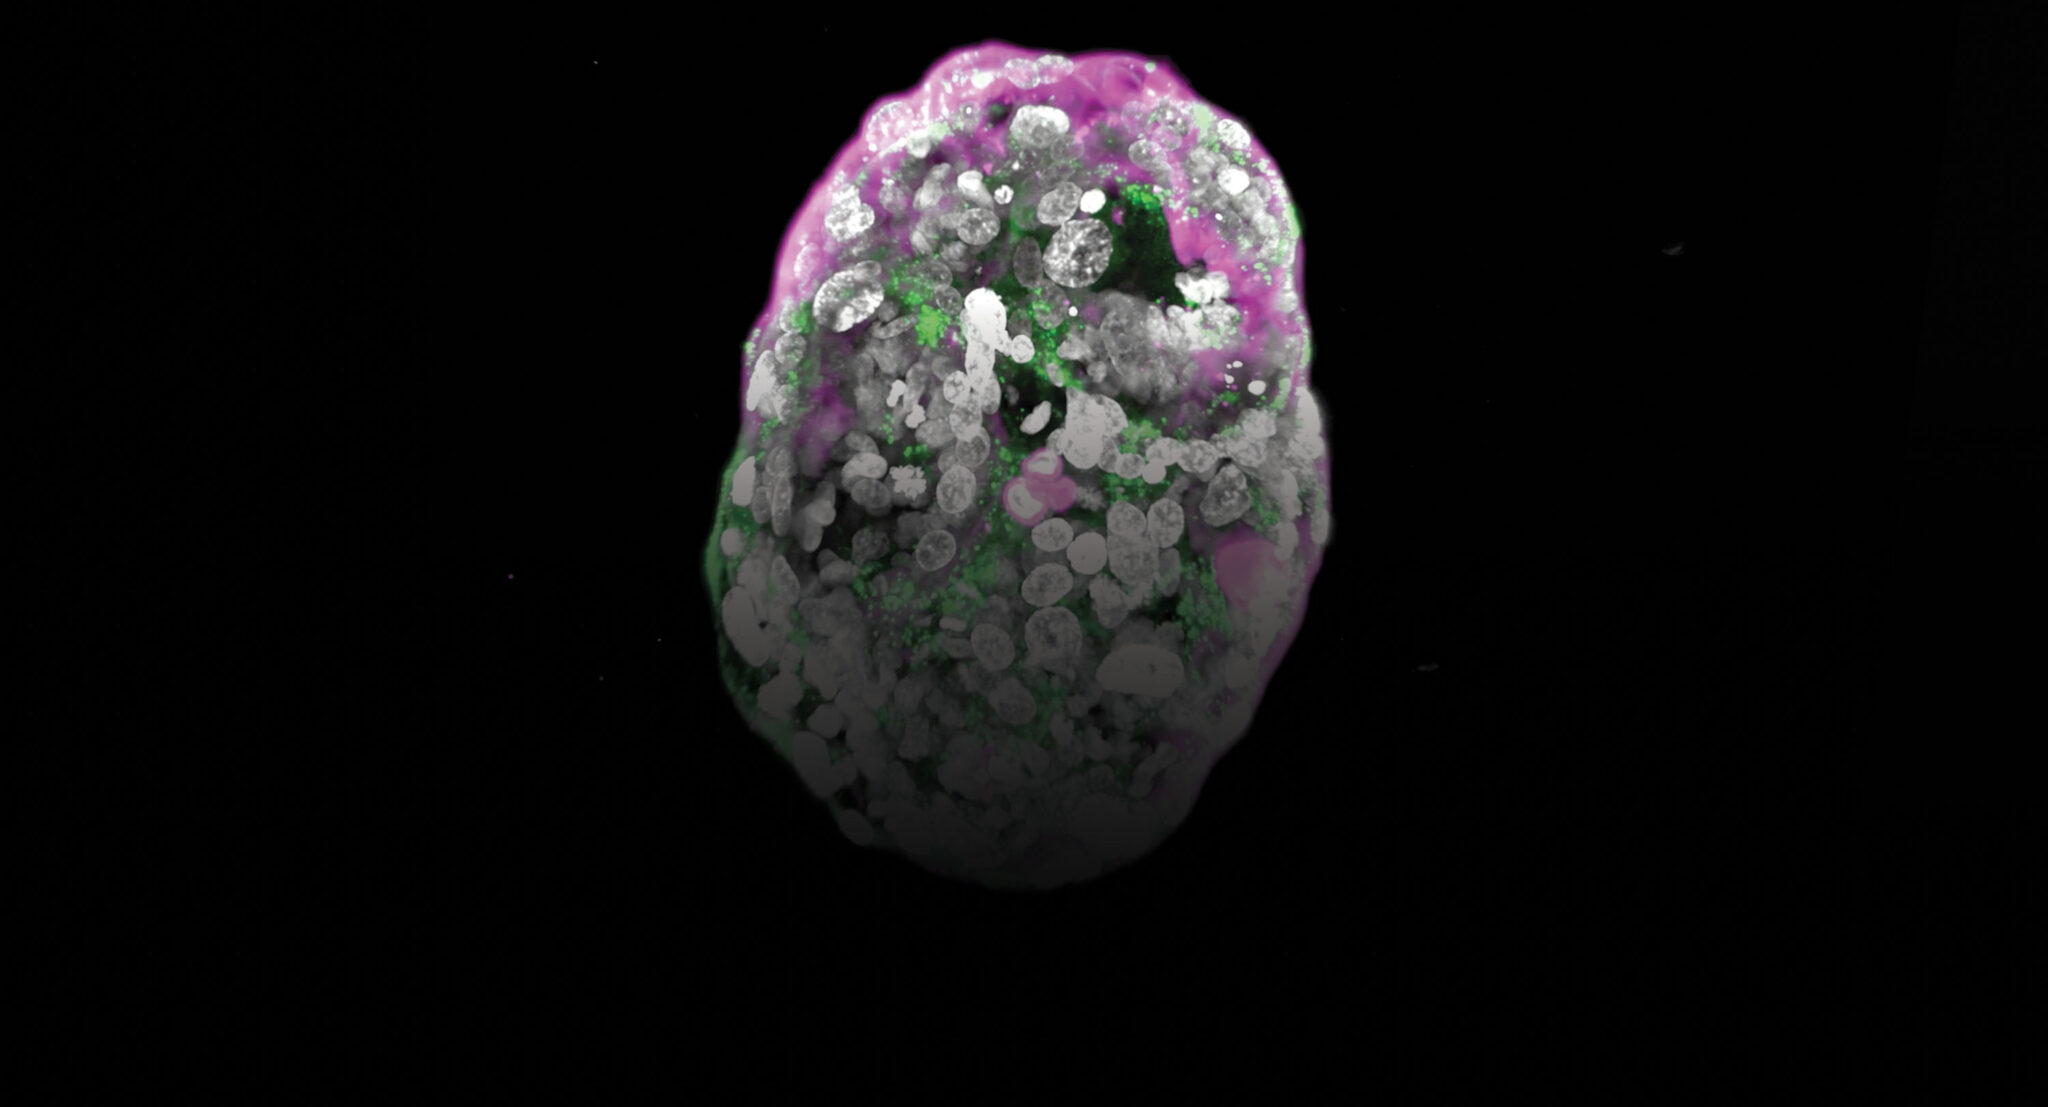

제이컵 한나(Jacob Hanna)의 연구실에서 줄기세포로 만들어진 이 ‘모델’은 임신 2주 된 인간 배아와 유사한 모습을 보인다.

형광 추적 물질은 임신 테스트기로 검출되는 호르몬이 존재하는 부위(초록색)와, 앞으로 태반으로 발달할 층(분홍색)을 강조해 보여준다.

출처: 와이즈만 과학연구소(Weizmann Institute of Science) 유튜브

The astonishing embryo models of Jacob Hanna